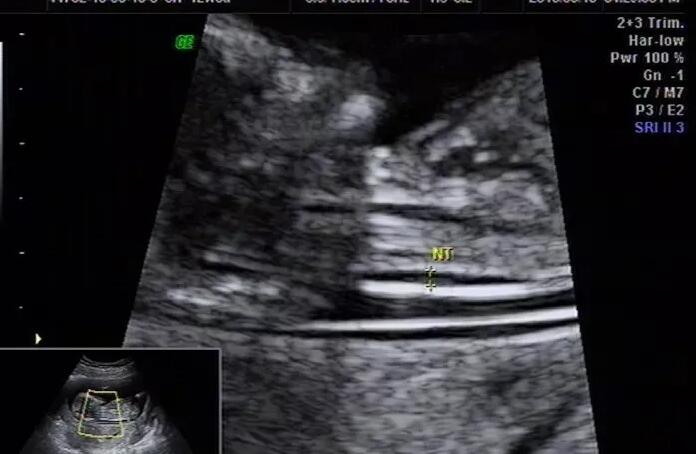

温州试管供卵 温州借卵试管成功率前三医院公开 ‘孕9周宝宝彩超图男宝女宝的